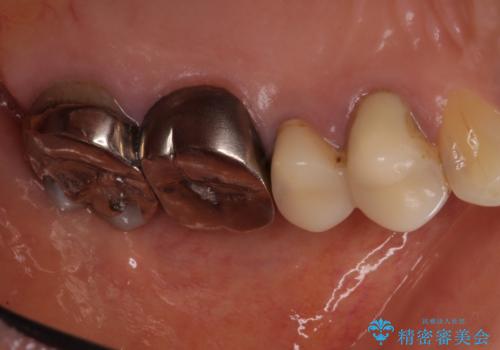

- 目立つ銀歯を気にして来院された患者様です。

奥歯を中心に銀歯が多く装着されており、一部の歯は咬合時に痛みを感じている状態でした。

必要な歯に根管治療を行い、オールセラミッククラウンにて補綴治療を行うこととしました。